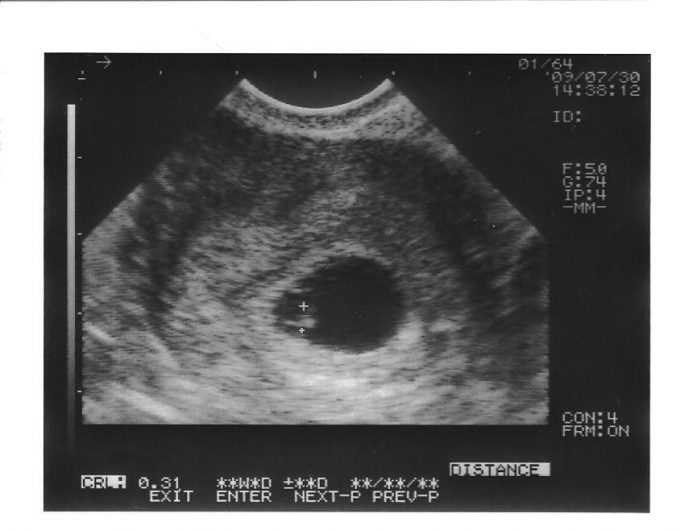

После измерения ХГЧ в крови пациентки на 14 дней после подсадки эмбрионов уже можно проводить УЗИ, но обычно его делают несколько позже. Конкретных инструкций, когда именно следует выполнять это исследование, нет.

Большинство специалистов считают целесообразным проведение УЗИ после ЭКО через 21 день, другие – спустя 28 суток.

Но отправляют на исследование только после положительного анализа на ХГЧ. В некоторых учреждениях и клиниках ведущие пациентку врачи назначают ультразвуковое исследование через шесть недель. Тогда уже можно увидеть на мониторе зародыш и услышать его сердцебиение.

После пересадки эмбрионов до первого УЗИ проходит только 3 недели, поэтому применяется трансвагинальный способ исследования. Он наиболее точно показывает количество зародышей, их расположение, плодное яйцо.

Как правило, процедуру назначают на 21-28 день после переноса эмбриона в организм матери при повышенном уровне ХГЧ. В некоторых медицинских учреждениях первое УЗИ назначают лишь спустя 6 недель после подсадки эмбрионов. На этом сроке будущего малыша можно четко увидеть на экране и услышать его сердцебиение.

Что видно на УЗИ на 20 день после переноса?

Первое УЗИ после ЭКО назначают примерно на 20-й день после пересадки. Оно покажет место имплантации эмбриона. Важно, чтобы эмбрион остался в матке, а не проник, например, в фаллопиеву трубу. Также исследование подтвердит количество прижившихся эмбрионов.